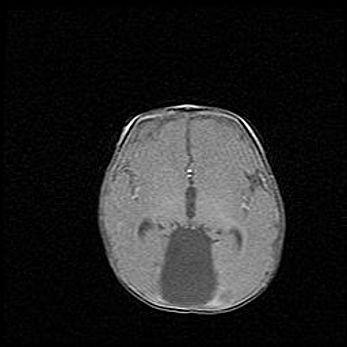

Наружная гидроцефалия с возможной атрофией височных областей.

Возраст: 28 дней

Вес: 3670 г

Пол: мужской

Окружность головы: 38 см

Срок гестации: 40 недель

Гидроцефалия головного мозга у новорожденных – это заболевание, которое характеризуется скоплением избыточного количества спинномозговой жидкости в желудочковой системе головного мозга в результате затруднения её перемещения от места выработки к месту поглощения в кровеносную систему или вследствие нарушения абсорбции. При открытой наружной форме гидроцефалии у новорожденных расширяются и переполняются субарахноидные пространства.

При нормотензивных  формах,  которые,  как  правило,  являются  следствием  перенесенных ишемических  повреждений  паренхимы  мозга,  возможно  сочетание микроцефалии  с нормотензивной гидроцефалией. В основе данных изменений лежит атрофия больших полушарий с преимущественной  локализацией  в  лобно-височных  областях.